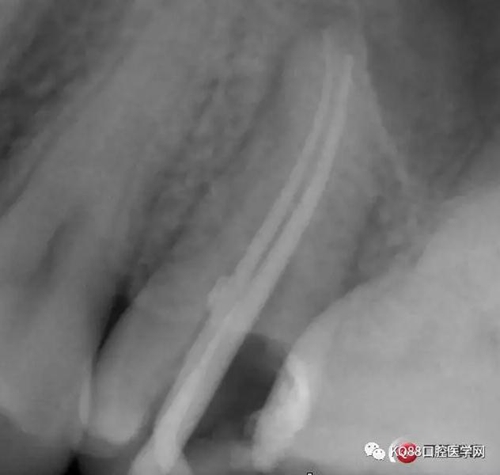

當(dāng)我第一次完成操作后,再次拍了一個(gè)插針片,發(fā)現(xiàn),距離根尖孔有1.5mm,書(shū)上說(shuō)的是2mm安全區(qū),可能如果隨意點(diǎn),就直接充填了,我想說(shuō)明的是,我們做根管,千萬(wàn)不要馬虎,不要湊合,一定嚴(yán)謹(jǐn)?shù)膽B(tài)度,于是我重新再回到C銼,再開(kāi)始耐心的預(yù)備,完成之后,再拍攝了插針片。

此次明顯可以看見(jiàn)根尖分開(kāi)了兩個(gè)根尖孔,根管治療永遠(yuǎn)就只是那一點(diǎn),如果都只是隨便做一下,我相信,沒(méi)有復(fù)雜的牙齒,根管治療都會(huì)很簡(jiǎn)單,態(tài)度決定一切,我不敢說(shuō)我做的會(huì)很好,但是我會(huì)靜下心來(lái),慢慢操作,這樣才能做得對(duì)的起自己和患者。于是根充完成,再次拍攝。